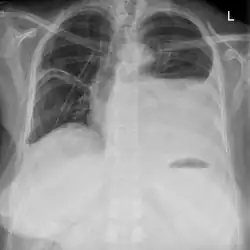

Pleuraerguss der linken Thoraxhälfte

Anzeichen eines Serothorax sind eine spürbare Dämpfung bei der Perkussion des Brustkorbes, ein nur geringes oder nicht wahrnehmbares Atemgeräusch sowie eine Verschattung des erkrankten Thoraxbereiches im Röntgenbild.[7]